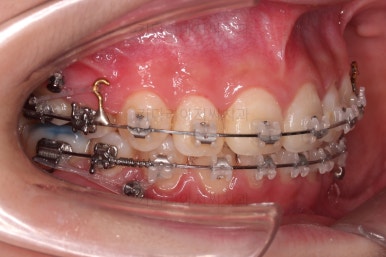

치아 갯수를 맞추고 튀어나온 앞니를 넣기 위해서 윗니 중간의 작은 어금니를 발치를 했고요.

아래는 통째로 앞으로 끌고 나오기로 했습니다.

아래턱은 아쉽게도 성장 시킬 수 있는 나이는 지났고, 대신 가능한 선에서 아랫니를 앞으로 빼보기로 했습니다.

윗니는 틈을 점점 줄여가고요.

아랫니는 중간에 오히려 틈이 생기고 있죠?

이런 효과로 위아래 앞니는 급속도로 가까워지게 됩니다.

아랫니는 이후에 어금니를 앞으로 당겨오면서 빈공간을 줄여 나갑니다.